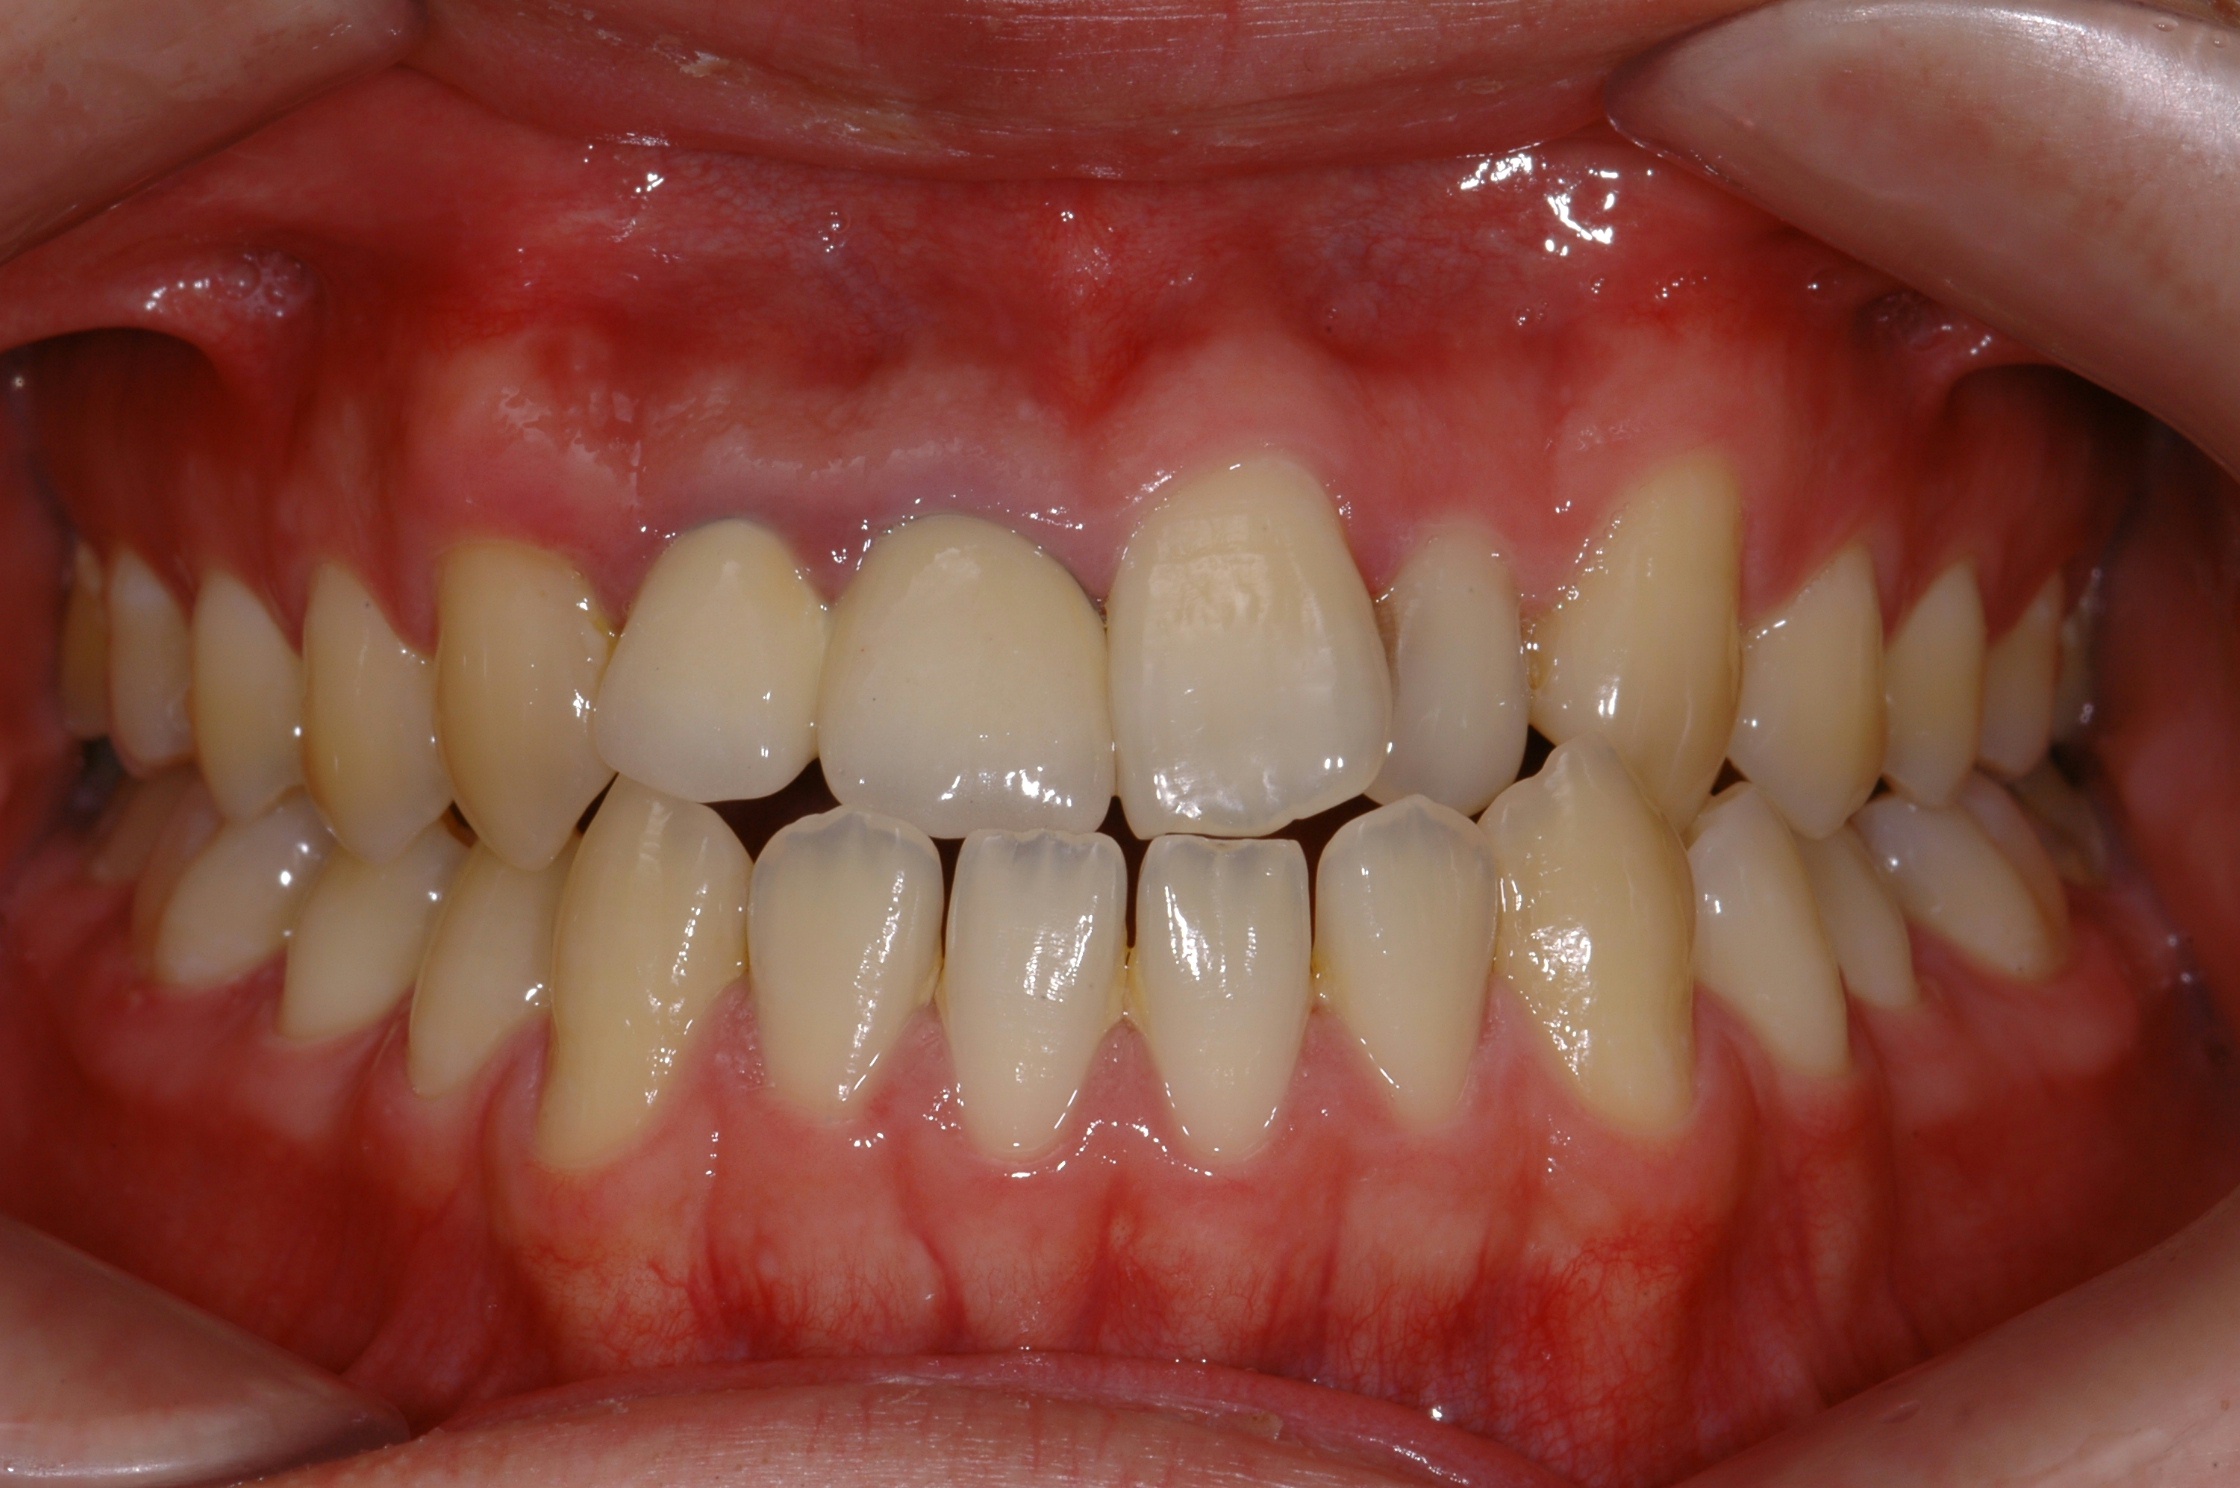

치료 전 사진입니다.